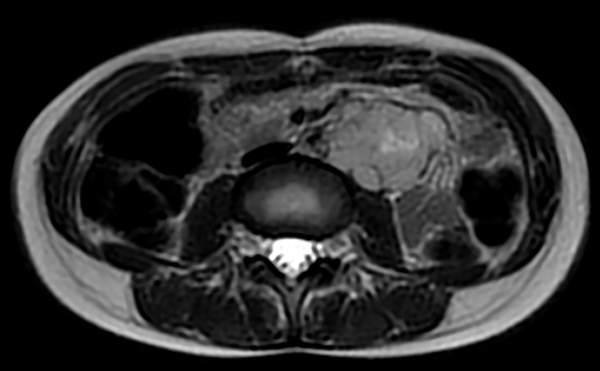

En la RMN se evidenció la presencia de un área hiperintensa en unión bulbomedular por lo cual se solicitó RMN de columna cervical donde se observó una lesión hiperintensa en T2 longitudinalmente extensa compatible con enfermedad desmielinizante (fig. 1).

Figura 1. Resonancia magnética de columna cervical donde se observa una lesión hiperintensa en T2 longitudinalmente extensa (compatible con enfermedad desmielinizante).